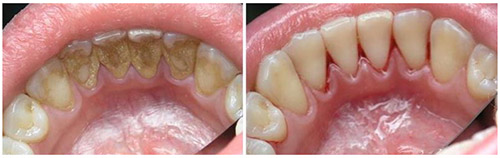

Кроме того, зубной камень может стать причиной неприятного запаха изо рта, изменения цвета зубов и кровоточивости десен, что создает значительный эстетический дискомфорт. В целом, контроль за количеством и качеством зубных отложений является важнейшим аспектом профилактики кариеса и заболеваний пародонта. На следующем рисунке представлено, как выглядит зубной камень.

Среди достоинств лазерной чистки зубов можно выделить: высокую эффективность, отсутствие боли, а также безопасность для зубной эмали и десен. Однако использование дорогостоящего лазерного оборудования приводит к высокой стоимости данной услуги. Кроме того, не все стоматологические клиники располагают таким оборудованием. Ниже представлены фотографии до и после процедуры удаления зубного камня.